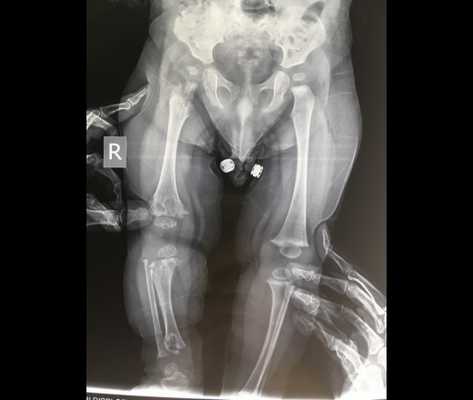

Метафизарная хондродисплазия (хряще-волосяная гипоплазия, СНН; тип Мак-Кьюсика, MIM 250250) - форма карликовости с короткими конечностями, возникающей в результате скелетной дисплазии. Скелетные особенности включают неполное разгибание в локтевом суставе, килевидная грудная клетка, искривление ног, удлинение малоберцовой кости относительно большеберцовой. У больных наблюдаются укорочение и утолщение кистей, разболтанные суставы кистей и стоп, недоразвитые ногти. При рентгенологическом исследовании выявляются изменения, названные метафизарным дизостозом: расширенные метафизы с фестончатым, неровно склерозированным краем. Биопсия выявляет гипоплазию хрящей. Волосы у больных тонкие, короткие, редкие, светлые. Поражаются также брови и ресницы. У многих больных имеются иммунологические дефекты, нарушается как клеточный, так и гуморальный иммунитет. Они чувствительны к инфекциям, могут иметь лимфопению, нейтропению, анемию. У некоторых больных нарушается кишечное всасывание, а также у них повышен риск опухолеобразования, преимущественно лимфом.

Для пациентов с типом MакКьюзика характерны хроническая анемия, патологии кишечника. На рентгеновских снимках заметно увеличение метафизов в области коленного сустава. В детском возрасте нередко встречается двояковыпуклое строение позвонков, которое постепенно исчезает после взросления.